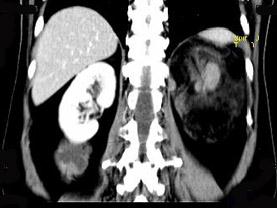

问题 女,64岁,左侧腰部胀痛,行CT扫描,下列说法正确的是()

选项 A.左肾区可见一巨大的占位性病灶,境界较清楚,胰腺尾部受压向前推移 B.该病灶密度不均匀,其内可见脂肪密度影,且呈不均匀强化 C.考虑为左肾来源的血管平滑肌脂肪瘤 D.考虑为左侧肾上腺来源的髓样脂肪瘤 E.考虑为腹膜后来源的脂肪肉瘤

答案 ABC